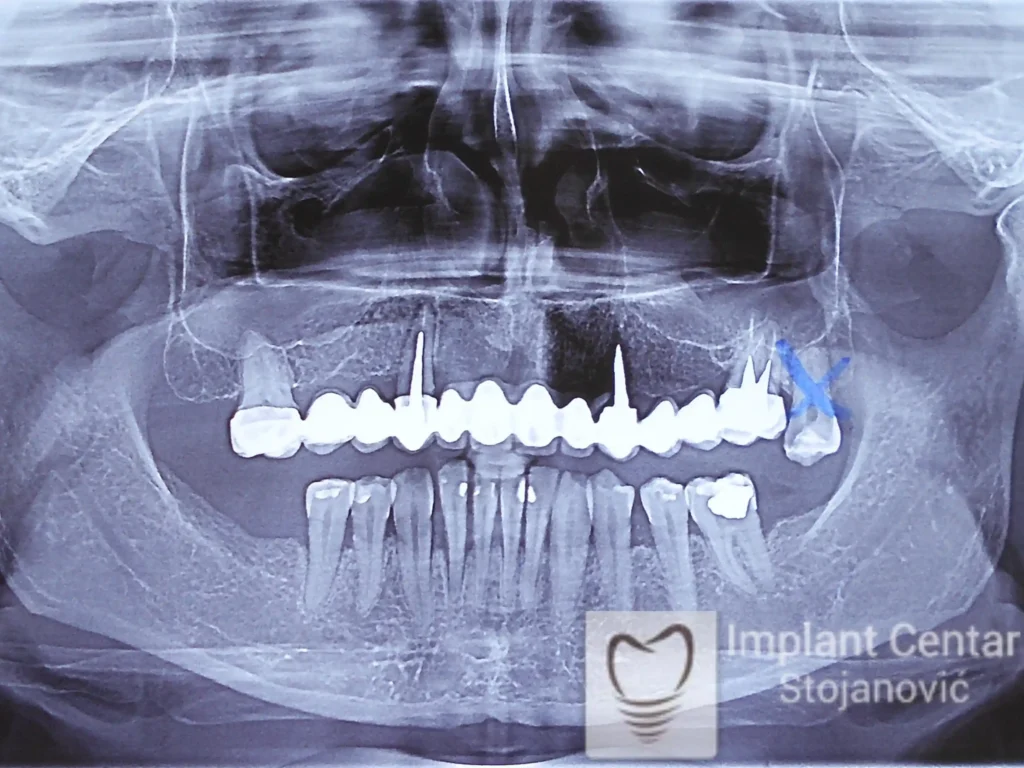

Na slici 1. slici 2. vidi se početno stanje — pacijent je imao prirodne zube, ali samo izradom novih mostova nije bilo moguće postići normalan odnos gornjih i donjih zuba (eugnatan zagrižaj).

Zbog toga je plan terapije uključivao vađenje svih preostalih zuba i ugradnju implantata u gornjoj i donjoj vilici. U gornjoj vilici postavljena su i dva tuberopterigoidna implantata, kao zamena za sinus lift proceduru, što se može videti na ortopan snimku nurađenom odmah nakon ugradnje (slika 3).